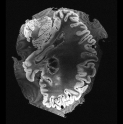

In neuroimaging, MRI tissue properties characterize underlying neurobiology, provide quantitative biomarkers for neurological disease detection and analysis, and can be used to synthesize arbitrary MRI contrasts. Estimating tissue properties from a single scan session using a protocol available on all clinical scanners promises to reduce scan time and cost, enable quantitative analysis in routine clinical scans and provide scan-independent biomarkers of disease. However, existing tissue properties estimation methods - most often $\mathbf{T_1}$ relaxation, $\mathbf{T_2^*}$ relaxation, and proton density ($\mathbf{PD}$) - require data from multiple scan sessions and cannot estimate all properties from a single clinically available MRI protocol such as the multiecho MRI scan. In addition, the widespread use of non-standard acquisition parameters across clinical imaging sites require estimation methods that can generalize across varying scanner parameters. However, existing learning methods are acquisition protocol specific and cannot estimate from heterogenous clinical data from different imaging sites. In this work we propose an unsupervised deep-learning strategy that employs MRI physics to estimate all three tissue properties from a single multiecho MRI scan session, and generalizes across varying acquisition parameters. The proposed strategy optimizes accurate synthesis of new MRI contrasts from estimated latent tissue properties, enabling unsupervised training, we also employ random acquisition parameters during training to achieve acquisition generalization. We provide the first demonstration of estimating all tissue properties from a single multiecho scan session. We demonstrate improved accuracy and generalizability for tissue property estimation and MRI synthesis.